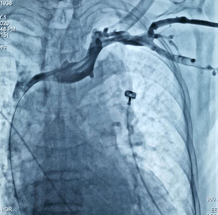

球囊扩张狭窄的左侧无名静脉

手术中 , 张煜程通过DSA下静脉造影 , 评估老人静脉狭窄的位置及狭窄程度 , 发现老人的左侧无名静脉出现狭窄 。

随后 , 他通过球囊扩张 , 缓慢谨慎地扩张了狭窄的血管 , 之前通行受阻的静脉血得以畅通进入心脏 , 成功疏通老人的“生命线” 。